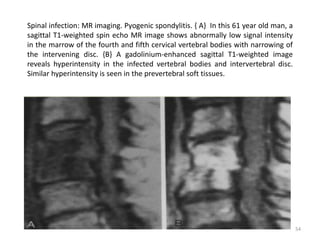

Spinal infection: MR imaging. Pyogenic spondylitis. { A} In this 61 year old man, a

sagittal T1-weighted spin echo MR image shows abnormally low signal intensity

in the marrow of the fourth and fifth cervical vertebral bodies with narrowing of

the intervening disc. {B} A gadolinium-enhanced sagittal T1-weighted image

reveals hyperintensity in the infected vertebral bodies and intervertebral disc.

Similar hyperintensity is seen in the prevertebral soft tissues.